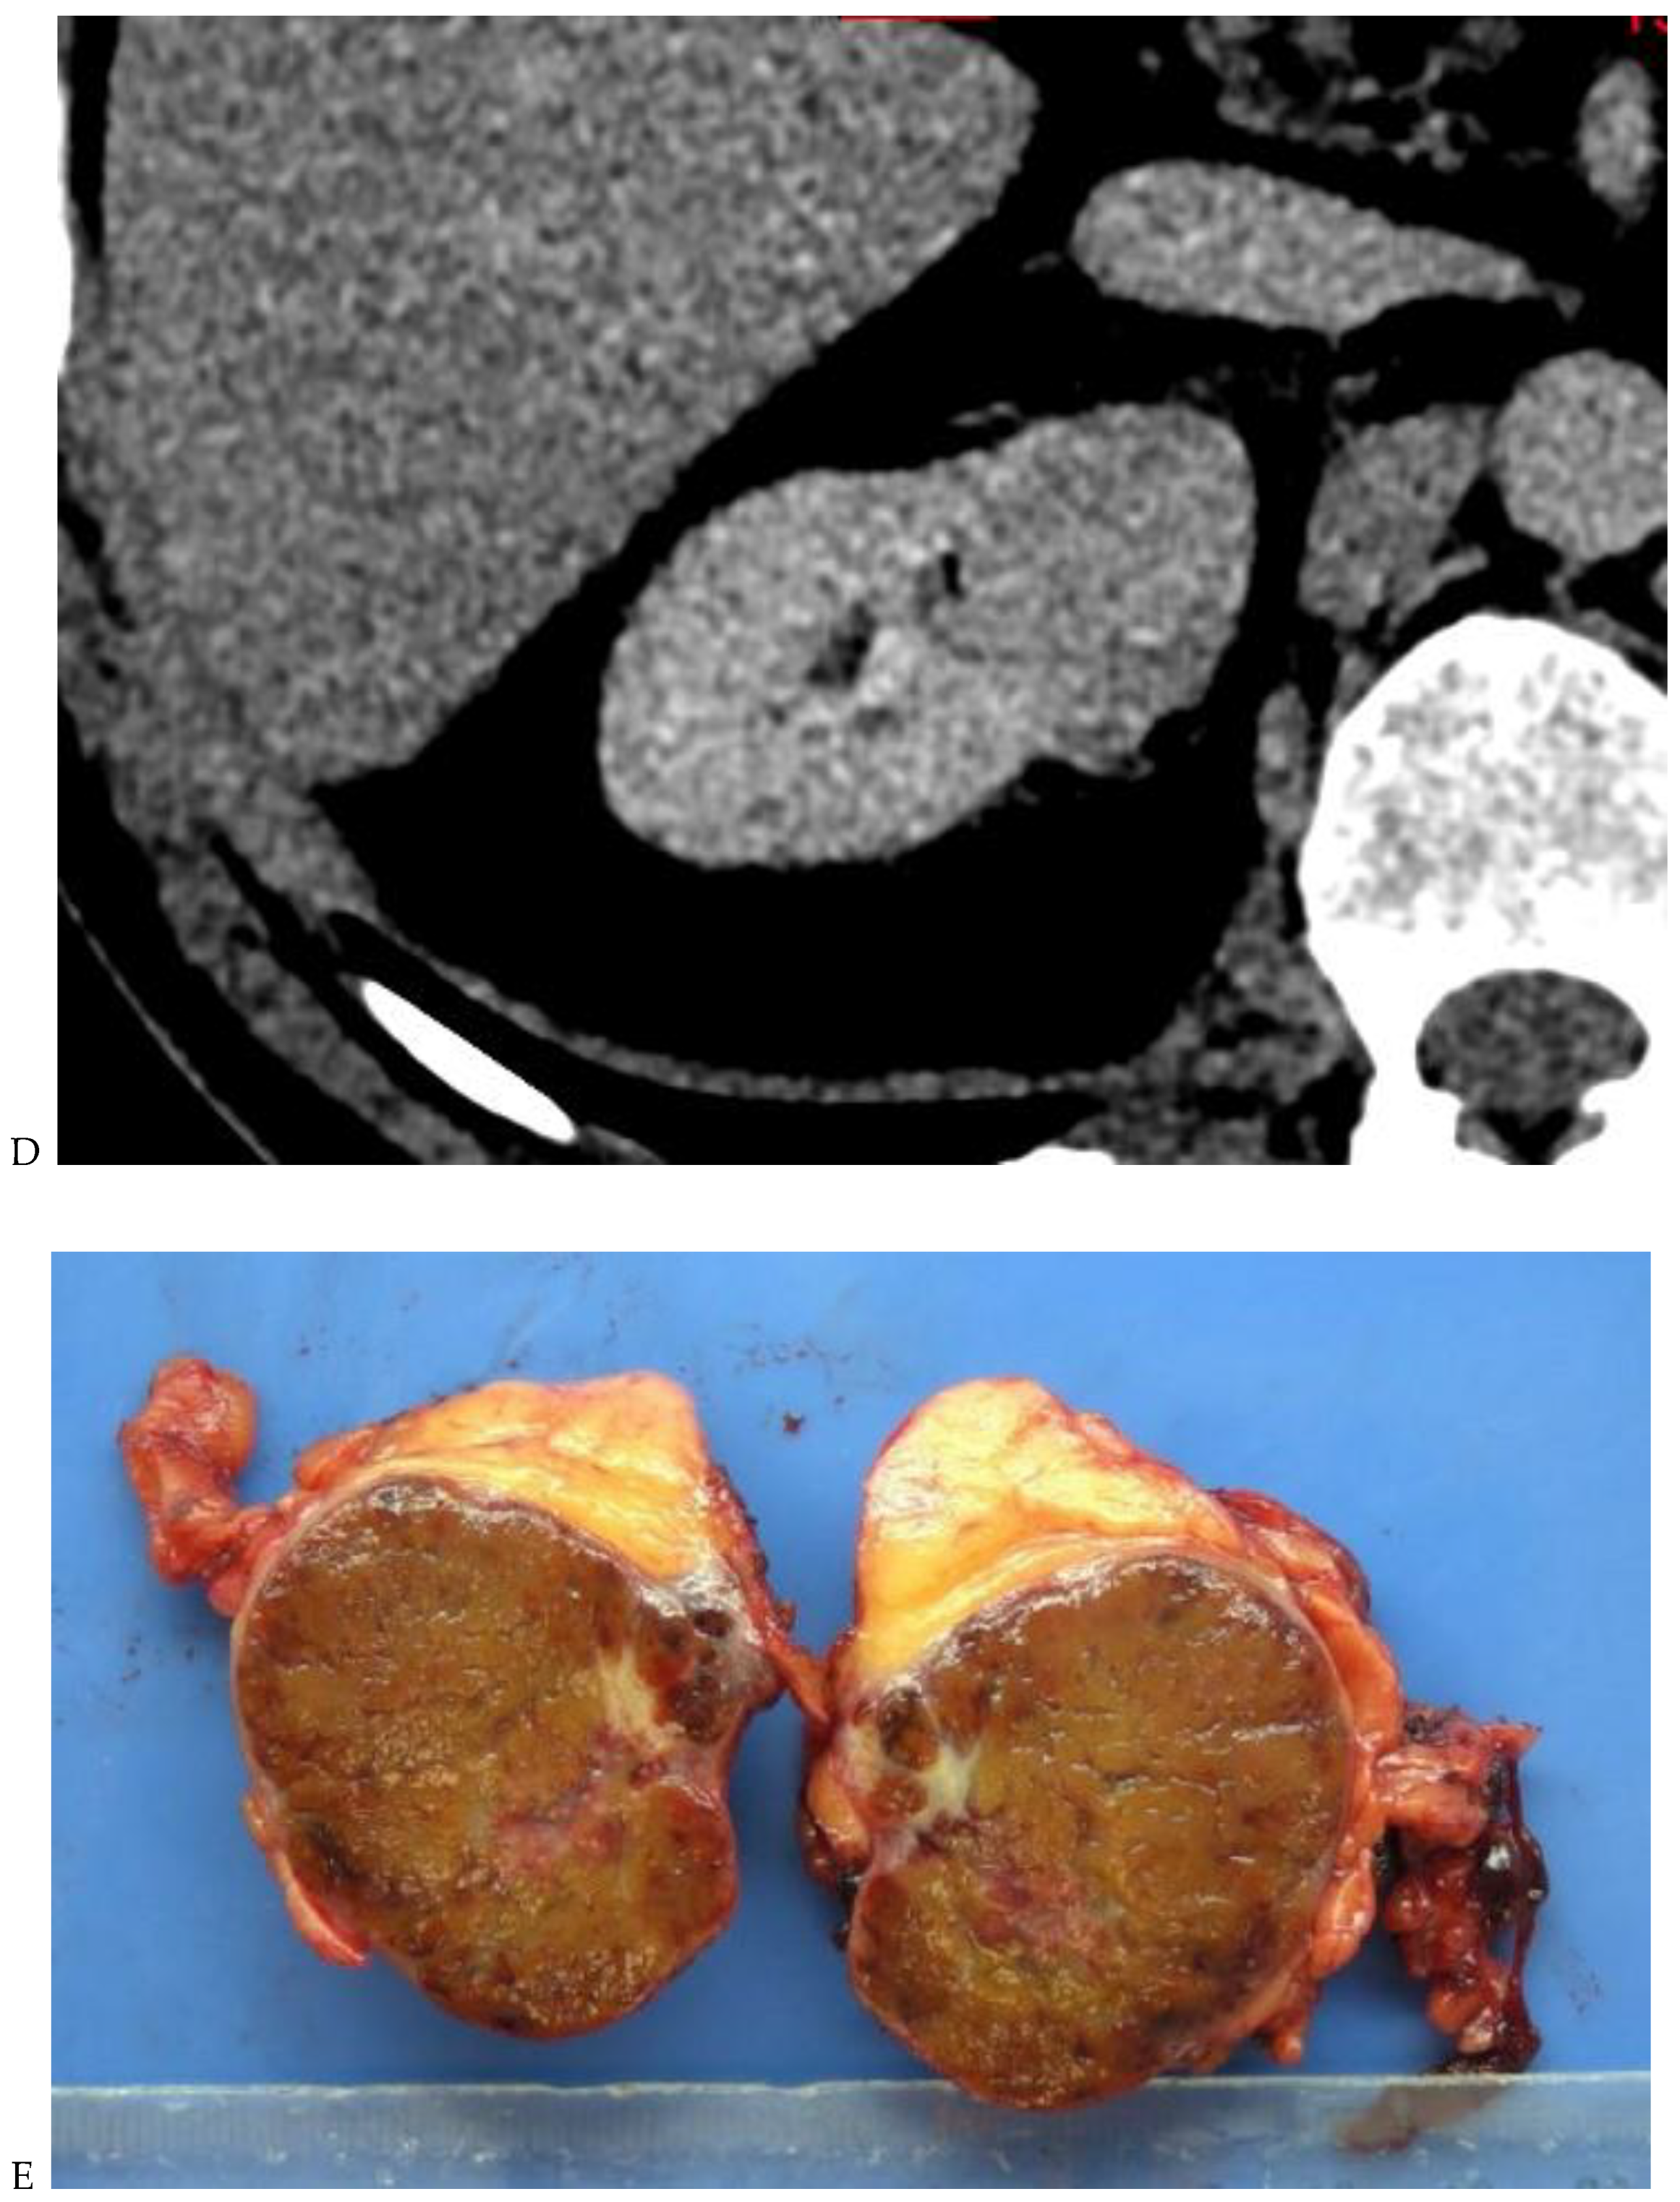

Oncocytoma in the right kidney of a 42-year-old man. (A) On the unenhanced image, the 4.8 cm lesion is isodense relative to the renal parenchyma. Enhancement is seen on the corticomedullary phase image (B), followed by washout on the nephrographic (C) and excretory (D) phase images. (E) Macroscopic view of the lesion after radical nephrectomy. Courtesy of Pr S. Ferlicot, Department of Pathology, Bicêtre.

CT aspect of a chromophobe renal cell carcinoma in the left kidney of a 68-year-old-woman. (A) Unenhanced image. Presence of an isodense, homogeneous solid lesion at the medium part of the left kidney. (B) It appears moderately hypervascularized on the corticomedullary phase image, with hyperdense septa. (C) There is progressive washout on the nephrographic phase image and the lesions appears hypodense relative to the renal parenchyma (C). (D) Macroscopic view of the lesion after partial nephrectomy. Courtesy of Pr S. Ferlicot, Department of Pathology, Bicêtre Hospital.